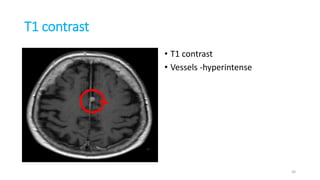

T1 contrast

• T1 contrast • T1 contrast

• Vessels -hyperintense